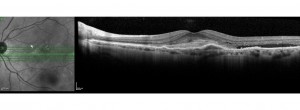

Ensayo clínico OAKS-DERBY: Eficacia y seguridad de pegcetacoplan en el tratamiento de la atrofia geográfica secundaria a DMAE